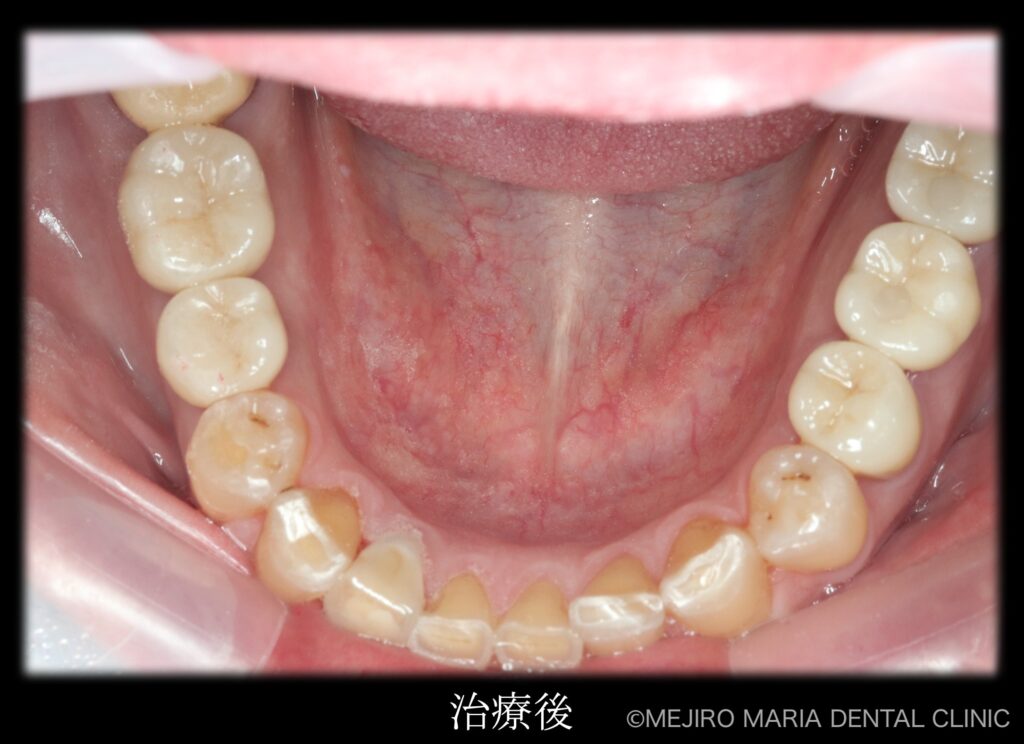

治療後の様子

各分野の専門医(精密根管治療専門医・インプラント専門医・口腔外科専門医)が最善を尽くすことで、より高度な治療をスピーディーに終えることができました。

最終段階に入る前に、仮歯の状態で咬合の安定が確認できたことから、最終補綴処置を行いました。最終補綴処置後の経過は良好で、今後はメンテナンスをしながらインプラントを含めた根尖周囲組織、補綴物(被せ物)の長期的な経過を確認していきます。